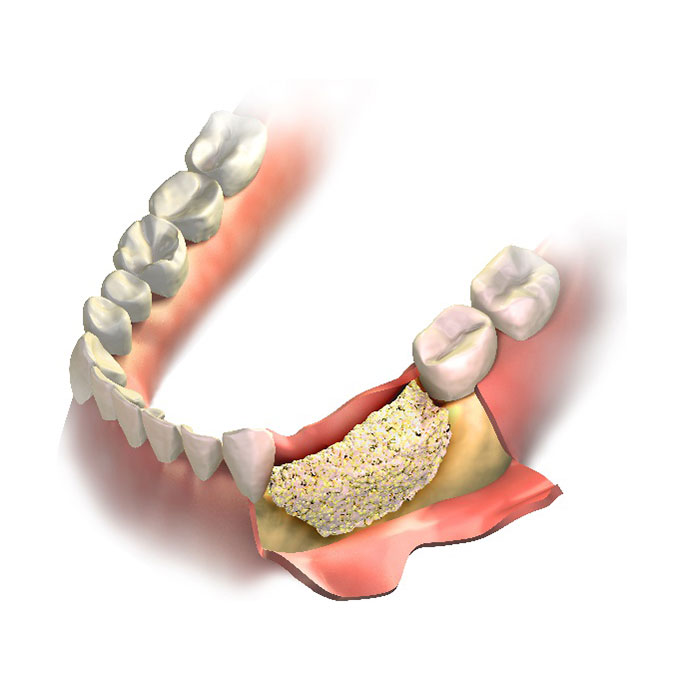

Bone Grafting

- In advanced periodontitis, damaged tooth roots may require a bone graft to restore bone, stabilize the tooth, and promote regrowth.

Bone Grafting

- In advanced periodontitis, damaged tooth roots may require a bone graft to restore bone, stabilize the tooth, and promote regrowth.